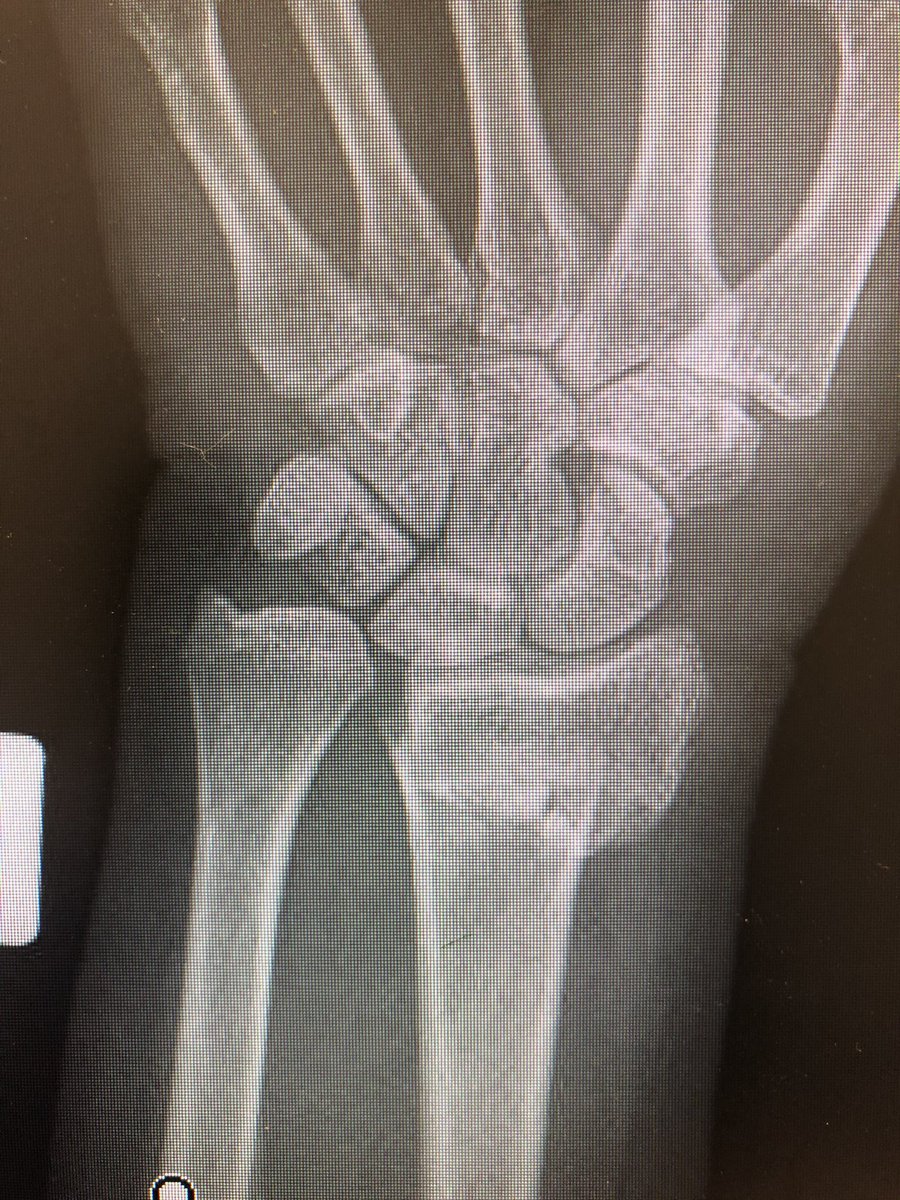

Simple everyday distal radius fracture. 60 yr old nurse. Medically well. #OrthoTwitter

I see conventionally this would be called an ‘extra-articular’ fracture.

Do we oversimplify this? Isn’t DRUJ a ‘joint’?

Isn’t the distal ulna getting all into the business of the carpals a ‘joint disruption’?

I would fix this.